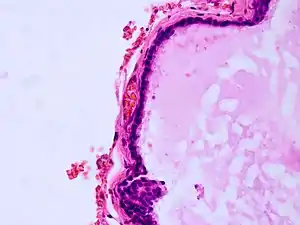

| Histopathology of colloid cyst |